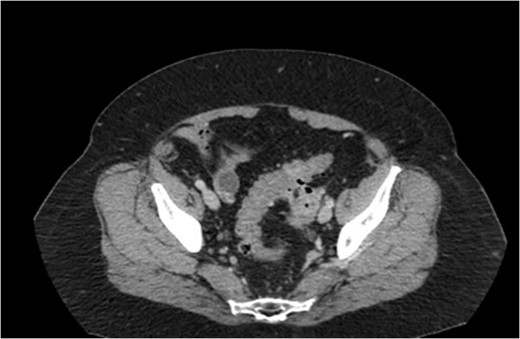

Two weeks later the patient was taken to the operating room for a hand-assisted laparoscopic colon resection and left oophorectomy. Intraoperatively, there were adhesions between the sigmoid colon and left anterolateral pelvic sidewall. Figure 3 shows the inflamed left ovary and fallopian tube adjacent to the sigmoid colon. The left ovary and a small portion of the left fallopian tube were dissected, and then resected en bloc with the sigmoid colon. Figure 4 depicts the uterus status post-resection. An end-to-end anastomosis was performed to the inraperitoneal rectum. The patient had an uncomplicated hospital course and was discharged home on post-operative Day number 2. One month later, the patient was doing well with normal bowel function, resolution of her UTI’s and resolved abdominal pain.